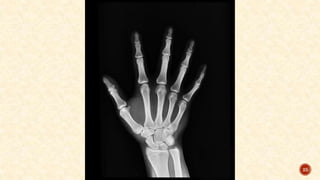

X-rays of both hands and of the affected joints:

Reduced joint space

Erosion of articular margins

Subchondral cysts

Juxta-articular rarefaction

Soft tissue shadow at the level of the joint because of joint effusion or synovial

hypertrophy

Deformities of the hand and fingers